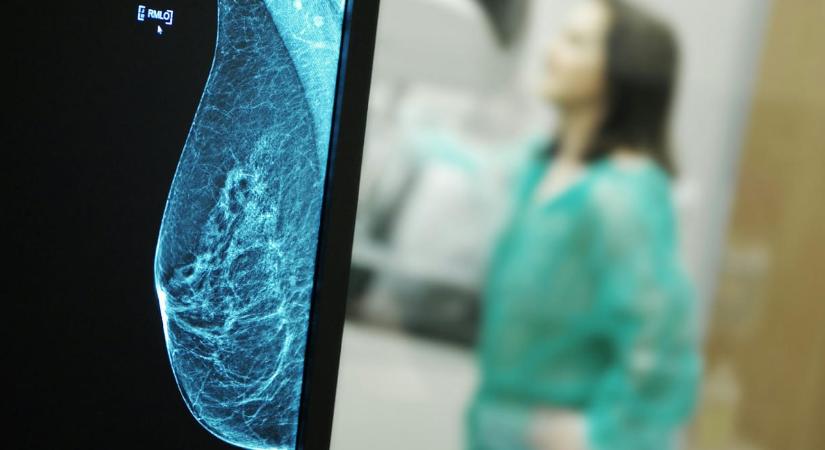

Brit és kanadai kutatók 3 millió sejtből álló térképet készítettek a női mellszövetről, és feltártak egy nem ismert összefüggést.